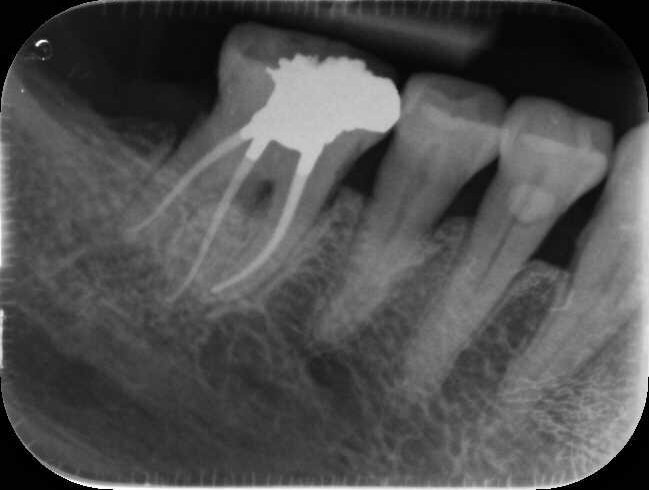

Fig. 17a: Case assisted with CBCT to determine anatomy pre-operatively. Note the multiple cross sections moving apically and the correlation to the 2-D view. Note also the conservative taper in relation to the root width. (Courtesy of Dr. Brett Gilbert)

Fig. 17b: Case assisted with CBCT to determine anatomy pre-operatively. Note the multiple cross sections moving apically and the correlation to the 2-D view. Note also the conservative taper in relation to the root width. (Courtesy of Dr. Brett Gilbert)

Fig. 17c: Case assisted with CBCT to determine anatomy pre-operatively. Note the multiple cross sections moving apically and the correlation to the 2-D view. Note also the conservative taper in relation to the root width. (Courtesy of Dr. Brett Gilbert)

Fig. 17d: Case assisted with CBCT to determine anatomy pre-operatively. Note the multiple cross sections moving apically and the correlation to the 2-D view. Note also the conservative taper in relation to the root width. (Courtesy of Dr. Brett Gilbert)

Fig. 17e: Case assisted with CBCT to determine anatomy pre-operatively. Note the multiple cross sections moving apically and the correlation to the 2-D view. Note also the conservative taper in relation to the root width. (Courtesy of Dr. Brett Gilbert)

Fig. 17f: Case assisted with CBCT to determine anatomy pre-operatively. Note the multiple cross sections moving apically and the correlation to the 2-D view. Note also the conservative taper in relation to the root width. (Courtesy of Dr. Brett Gilbert)

Managing complex anatomy is much simpler if the clinician has a pre-operative road map. The CBCT provides the roadmap and the surgical microscope the lens (literally) through which to visualize the result. Aside from a relaxed patient who is profoundly numb, being able to visualize anatomy by taking a pre-operative (and possibly intra-operative) CBCT and using a surgical microscope during treatment have no substitutes. They are the current “Gold Standard” in that 3-D imaging shows the clinician the true reality of a clinical situation as opposed to the suggestion gained from a 2-D radiograph. Proper interpretation of imaging prior to and/or during endodontic treatment goes a long way in taking the “guesswork” out of identifying canal location and other anatomical complexities as the procedure unfolds. In a 2014 study by El Fayad and Johnson, it was determined that when having a pre-operative CBCT as compared to 2-D radiographs alone, the treatment plan was modified 62 percent of the time. This is a huge game changer to think that the information learned from 3-D imaging changed the plan of treatment over six times out of 10 (Fig. 4).[2]